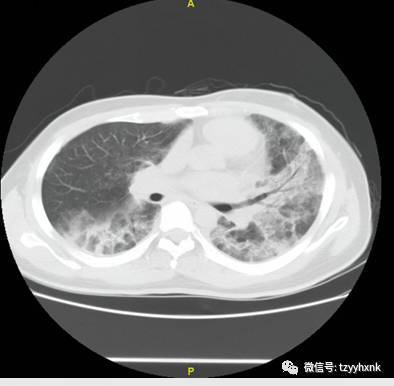

一例HIV抗体阴性的艾滋病合并肺孢子菌肺炎确